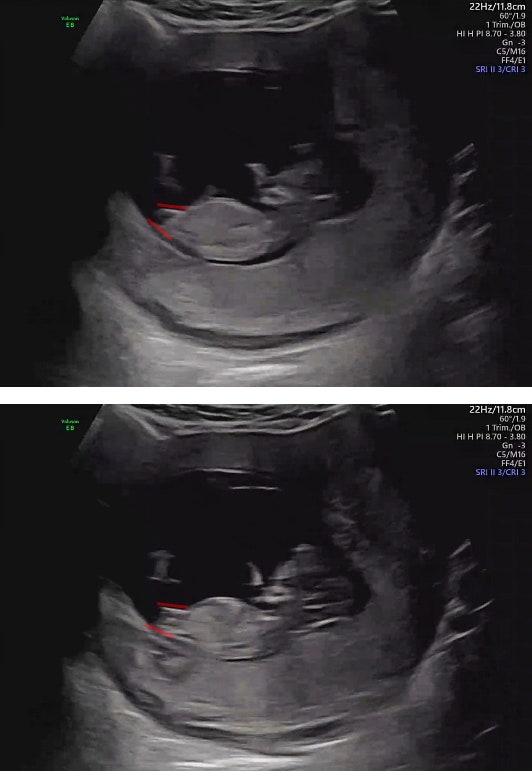

22주차 임신일기:) 임산부 복통 설사 구토 장염 증상, 맹장 의심 소견, 급성 소화기 염증

말도 많고 탈도 많은 우리 둘찌ㅎㅎ 지난 22주차에 맹장 의심 소견을 받은 이야기를 기록해본다. - 임신 22...